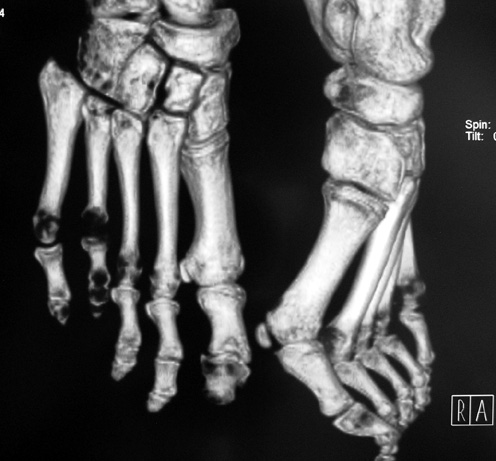

Finger (metacarpus) and toe (metatarsus) shortness can be seen congenitally as a single deformity or as a part of various syndromes; or after trauma or Freiberg disease (avascular necrosis). The frequency of congenital metacarpal or metatarsal shortness is less yhan 1/1000. It is seen 5 times more freqently in women and usually (72%) bilateral. Fourth finger is the most frequently involved. Although the cause of this problem is not known exactly, it is believed that the deformity is usually caused by early closure of the growth plate.

Surgical treatment may be required for metacarpal shortness because of cosmetic disturbance and fatigue in the dominant hand; and for metatarsal shortness because of cosmetic appearance, metatarsalgia, deformity due to dorsal shift of the short finger, pain and pressure ulcers due to plantar shift of the short finger, or difficulty in shoe wearing. Various techniques have been defined for the treatment of congenital metacarpal or metatarsal shortness. However, the most frequently used methods are acute lengthening with grafting, and distraction osteogenesis (callotasis). Callotasis method is preferred for lengthening more than 1 cm. In our department, we prefer distraction osteogenesis with unilateral or circular external fixator for lengthening of metacarpal and metatarsal bones.